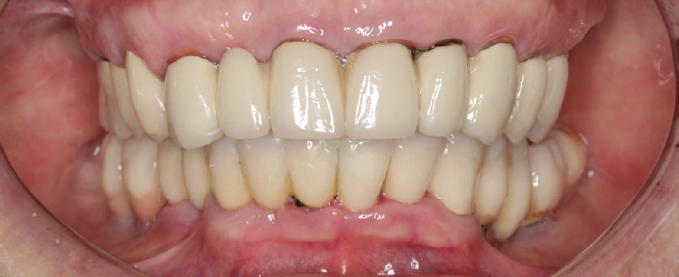

After 4 months of using the temporary structures, the fabrication and fitting of the permanent dentures with tooth and implant support were completed (Fig. 11).

Fig. 11. Permanent metal-ceramic structures based on the teeth and implants: a, anterior projection; b, occlusal projection of the upper dentition; c, occlusal projection of the lower dentition

Рис. 11. Постоянные металлокерамические конструкции с опорой на зубы и имплантаты: a — передняя проекция, b — окклюзионная проекция верхнего зубного ряда, c — окклюзионная проекция нижнего зубного ряда